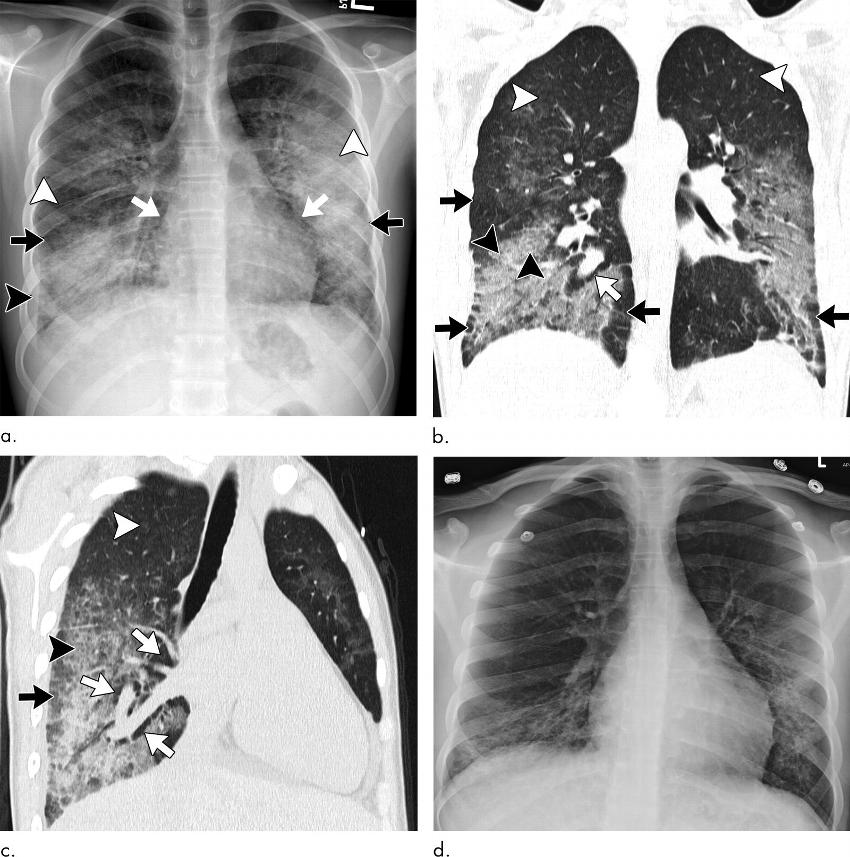

The study reports that in most cases, both the imaging and pathologic findings of EVALI are that of organizing pneumonia and diffuse alveolar damage, although the disease can appear differently on scans for some people.